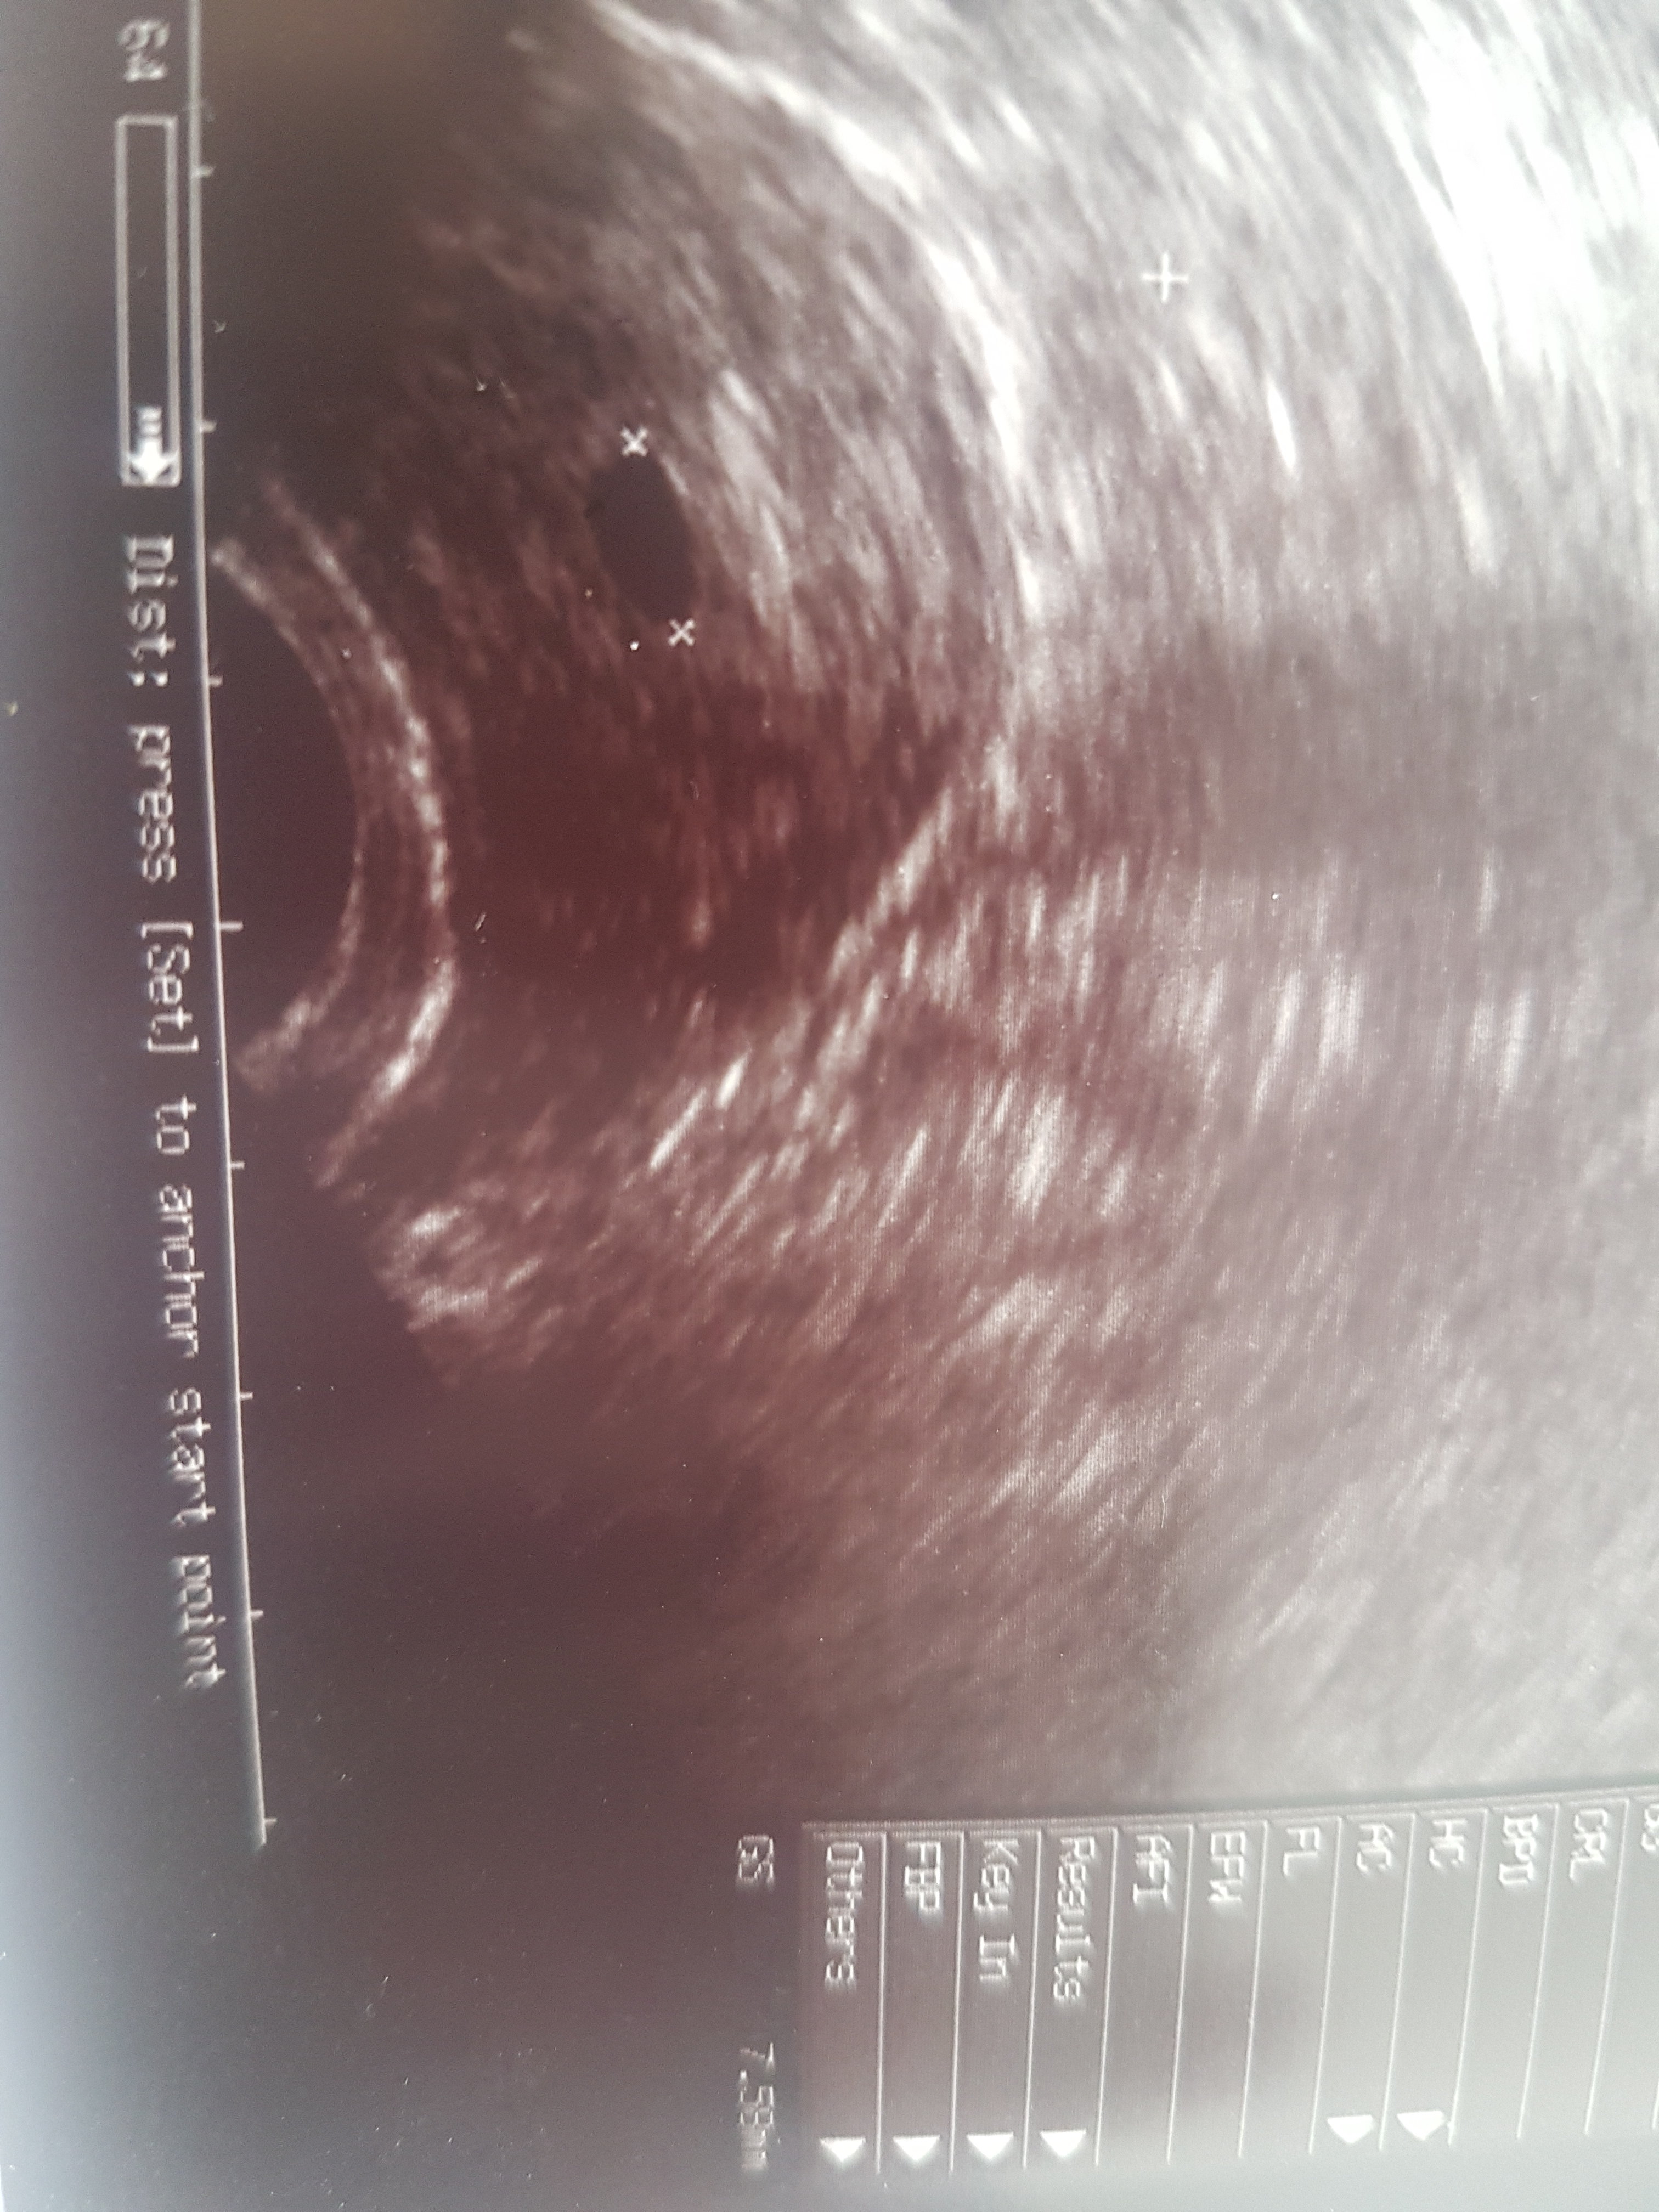

Byłam dzisiaj na przyspieszonej wizycie , dostałam letrox na zbicie TSH a przy okazji USG i mam i ja swojego kropka😀

Załączniki

• IMG_20200509_125341.jpg